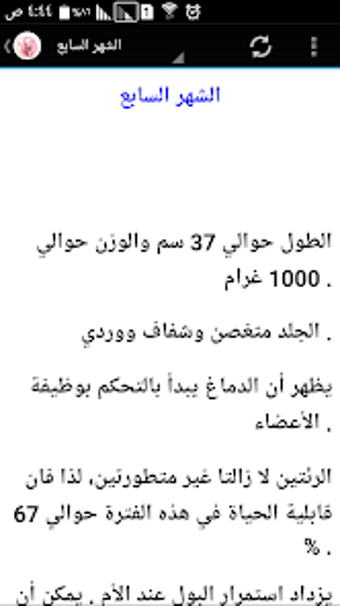

The Pregnancy and Birth Calculator App by metraqapps is a free Android utility tool app designed for expecting mothers. This app provides an extensive guide to pregnancy, including a month-by-month breakdown of fetal development, symptoms, and tips for a healthy pregnancy. The app also includes a pregnancy calculator to determine the due date and a contraction timer to help track labor.